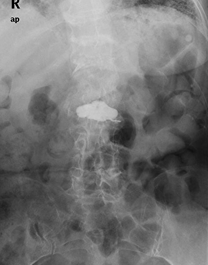

因:“腰椎骨折椎体成形术后2天”入院

患者因“脑卒中后遗症”在我中心康复治疗,于4月27日行走时滑倒腰部跌伤,当时即感疼痛,活动受限,到当地医院就诊,经CT等检查后,诊断为L3骨折,予卧床休息、口服活血化瘀及镇痛等对症治疗,患者自觉症状无改善,于6月03日在上级医院行椎体成形手术,2014年6月04日再次转入我中心继续康复治疗。患者入院时腰背部疼痛明显改善,并可下床活动。

神清,精神可,轮椅推入病房,精神略显紧张,发育正常,营养中等,呼吸平稳,查体合作,言语清晰,对答切题。全身皮肤粘膜无黄染,无皮疹、无淤斑、淤点,毛发分布正常,皮温正常、皮肤弹性正常,无肝掌。浅表淋巴结未及肿大。头颅大小正常,无畸形,眼睑无水肿,结膜无充血,眼球正常,无运动障碍,巩膜无黄染,角膜正常,双侧瞳孔等大等圆7.5px,对光反射正常。左侧鼻唇沟浅,左侧口角下垂,左侧额纹消失,耳廓正常,外耳道无脓性分泌物,乳突无压痛,双侧听力正常。鼻外形正常,鼻道畅,鼻中隔无偏曲,鼻旁窦无压痛。口唇红润无绀,口腔粘膜正常,舌正常,伸舌居中,牙龈无肿胀出血,咽无充血,双侧扁桃体未见肿大,声音正常。颈软,无抵抗,脑膜刺激征阴性,气管居中,颈静脉无充盈,双侧甲状腺未及肿大,无压痛。胸廓无明显畸形,乳头对称,双侧呼吸运动对称,语颤相等,叩诊清音,双肺呼吸音粗,未及明显干湿啰音。心前区未见异常隆起,心尖搏动位于左第5肋锁骨中线内12.5px,未及震颤,心相对浊音界正常。心率80次/分,律齐,各瓣膜听诊区未闻及病理性杂音。未及水冲脉、股动脉枪击音。腹平,未见腹壁静脉曲张,未见肠型蠕动波,腹软,无压痛、反跳痛,肝脾肋下未及,肾未触及,全腹未触及包块,肝肾区无叩痛,移动性浊音阴性,肠鸣音正常,5次/分。脊柱胸腰段后凸畸形,活动度轻度受限,棘突无明显叩痛,双下肢无水肿。四肢肌力正常,关节无畸形。双下肢感觉正常。

入院诊断:(1)腰椎骨折术后